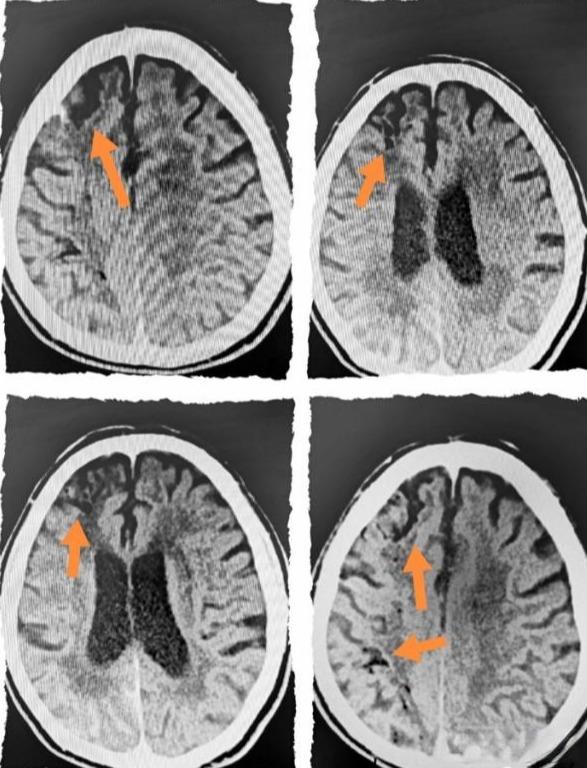

然而,空气栓塞的诊断并不总是直截了当。在紧急情况下,医生可能会首先考虑更常见的并发症,如脑出血或血栓形成。但通过仔细检查和必要的影像学检查,如头颅CT或MRI,通常可以发现空气栓塞的特征性表现。